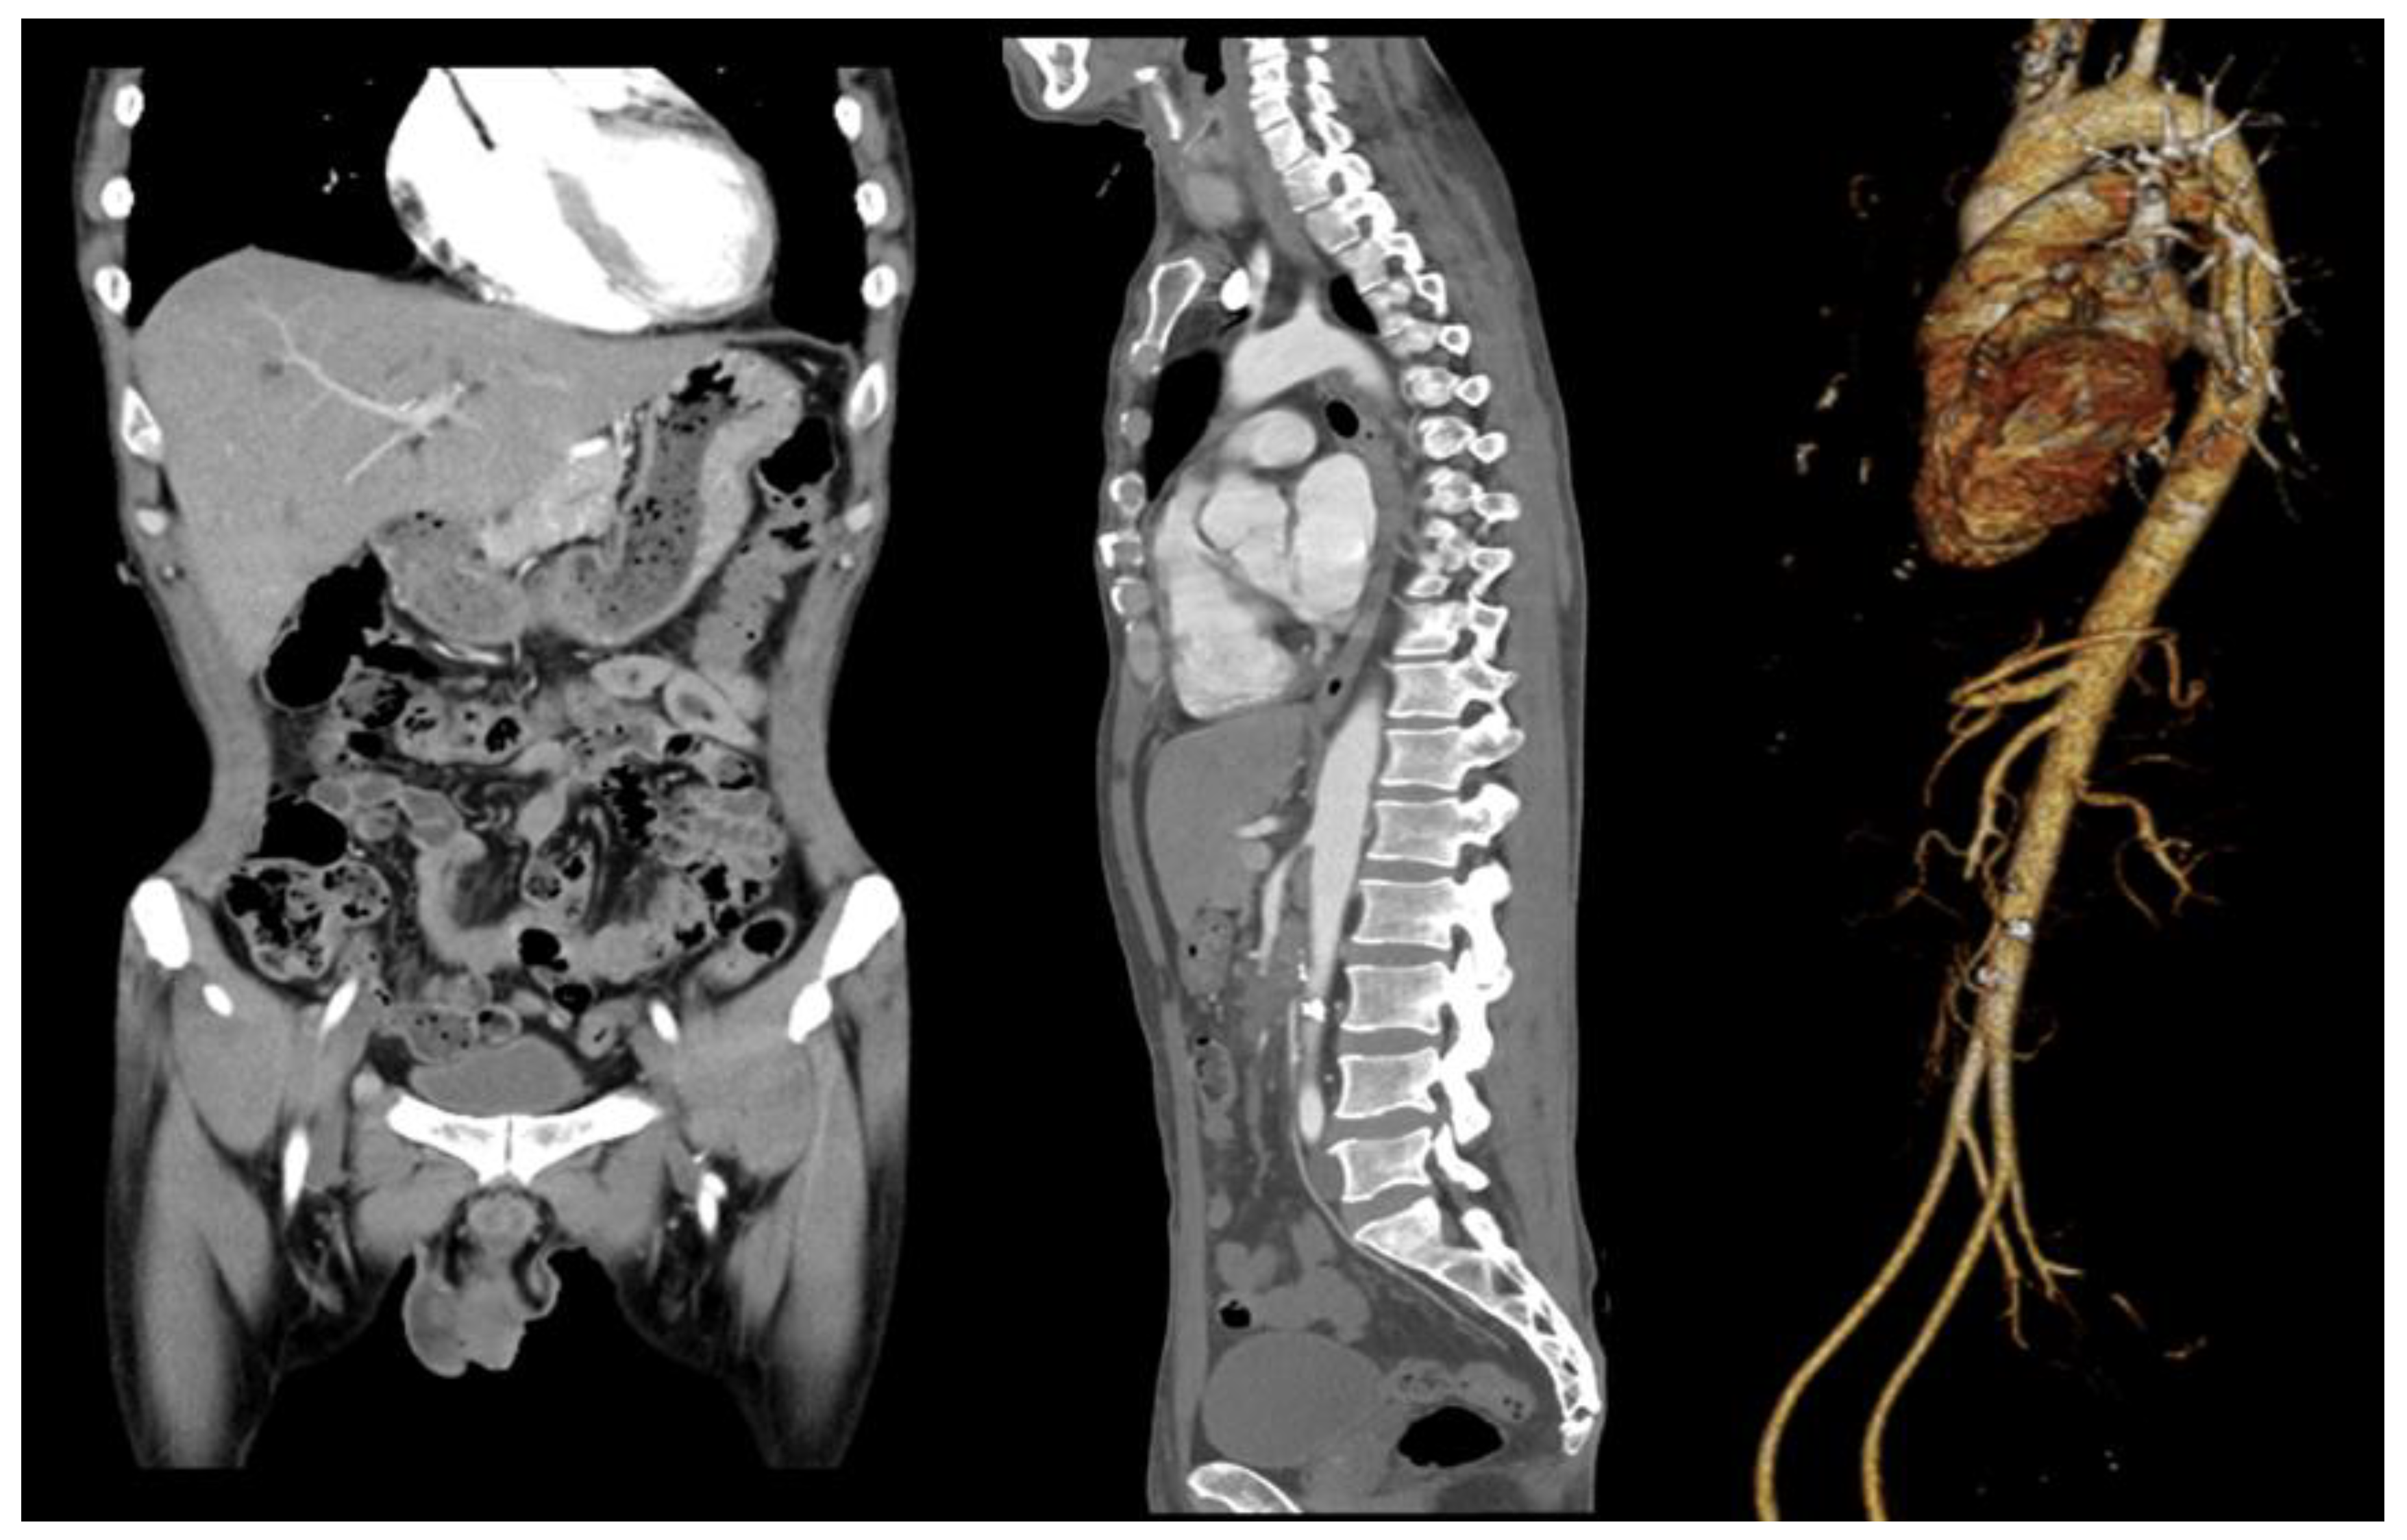

6.4. The Patient Was Diagnosed with SMA Aneurysm Using Abdominal CT, Which Was Followed by Persistent Abdominal Pain and Fever—Surgery Was Performed on the Transplanted Vessel